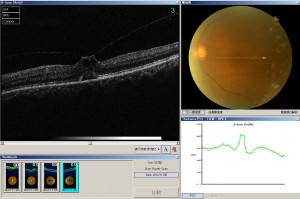

硝子体黄斑牽引症候群

後部硝子体剥離が網膜の一部分のみが残り,この残った部分が引っ張られることがあります.これが網膜のうち最も大切な黄斑で起こるのが硝子体黄斑牽引症候群です.類似疾患として網膜前膜黄斑円孔偽黄斑円孔があります.

症状は物の歪み,光視症,中心の物が小さく見える等があります.治療として硝子体手術がありますが,自然経過で残った部分が剥がれ,治癒することもあります.